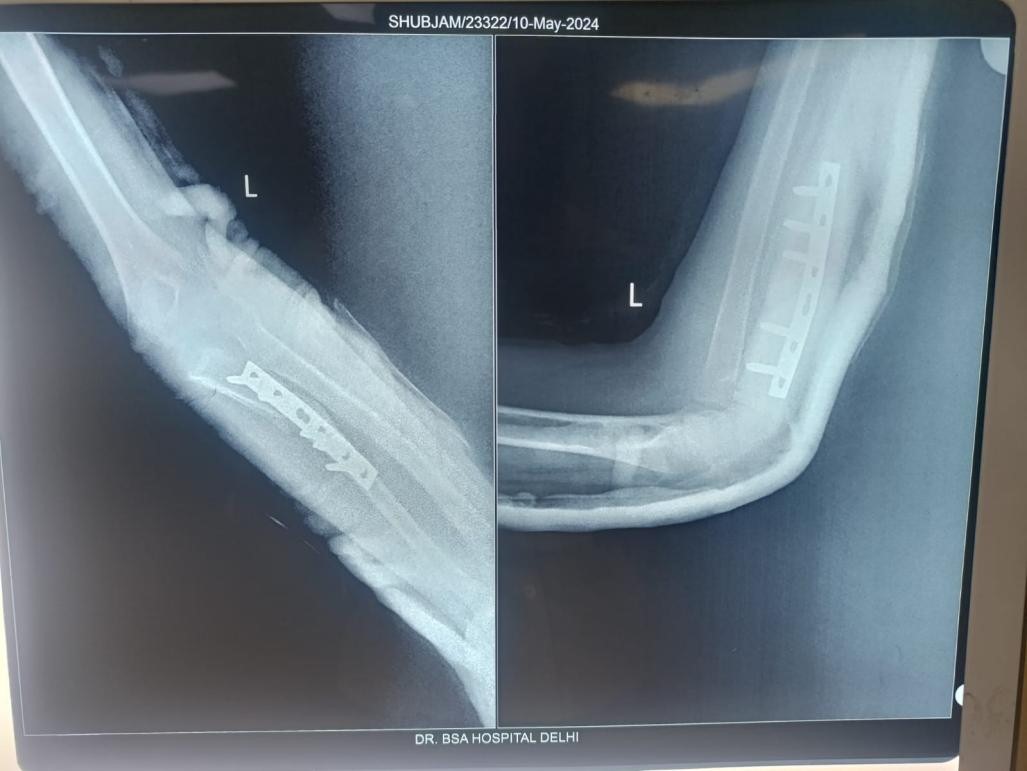

Postoperatively, the upper limb was immobilized in a cast with the elbow flexed at 90° and the forearm supinated for 4–6 weeks. After confirming stability with follow-up imaging, K-wire removal was performed, followed by a structured rehabilitation program emphasizing progressive mobilization and strengthening (Fig. 3). All patients additionally underwent a supervised institutional shoulder rehabilitation protocol to improve ROM and rotator cuff strength. Monitoring continued for at least 48 weeks, after which plate removal was considered. An additional evaluation was performed 8 weeks following implant removal.

Figure 3: Post-operative radiograph showing radial head reduction.